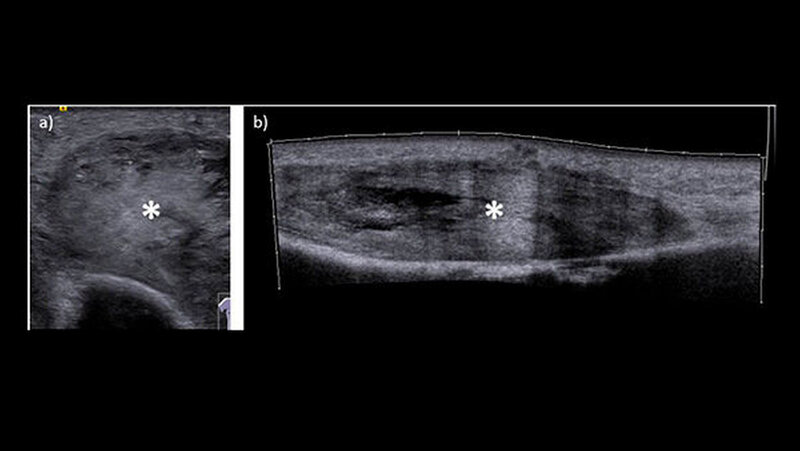

Ein Jahr nach der Exzision des Primärtumors, der begleitenden Radiatio sowie dem mikrochirurgischenAufbau des Unterkieferdefekts stellte sich der Patient erneut vor, um einen Termin zur Entfernung des Osteosynthesematerials zu vereinbaren. Bei dieser Untersuchung bemerkten die Chirurgen eine erhebliche Raumforderung am linken Oberarm, die nach Angaben des Patienten sehr schnellem Wachstum.

Röntgen und MRT sind nicht eindeutig

Weder das Röntgenbild noch die weitere Untersuchung mit magnetresonanztomografischer Bildgebung gaben eindeutigen Aufschluss. Daraufhin wurde eine Biopsie veranlasst, die die Verdachtsdiagnose einer Metastase des oralen Plattenepithelkarzinoms histologisch bestätigte.